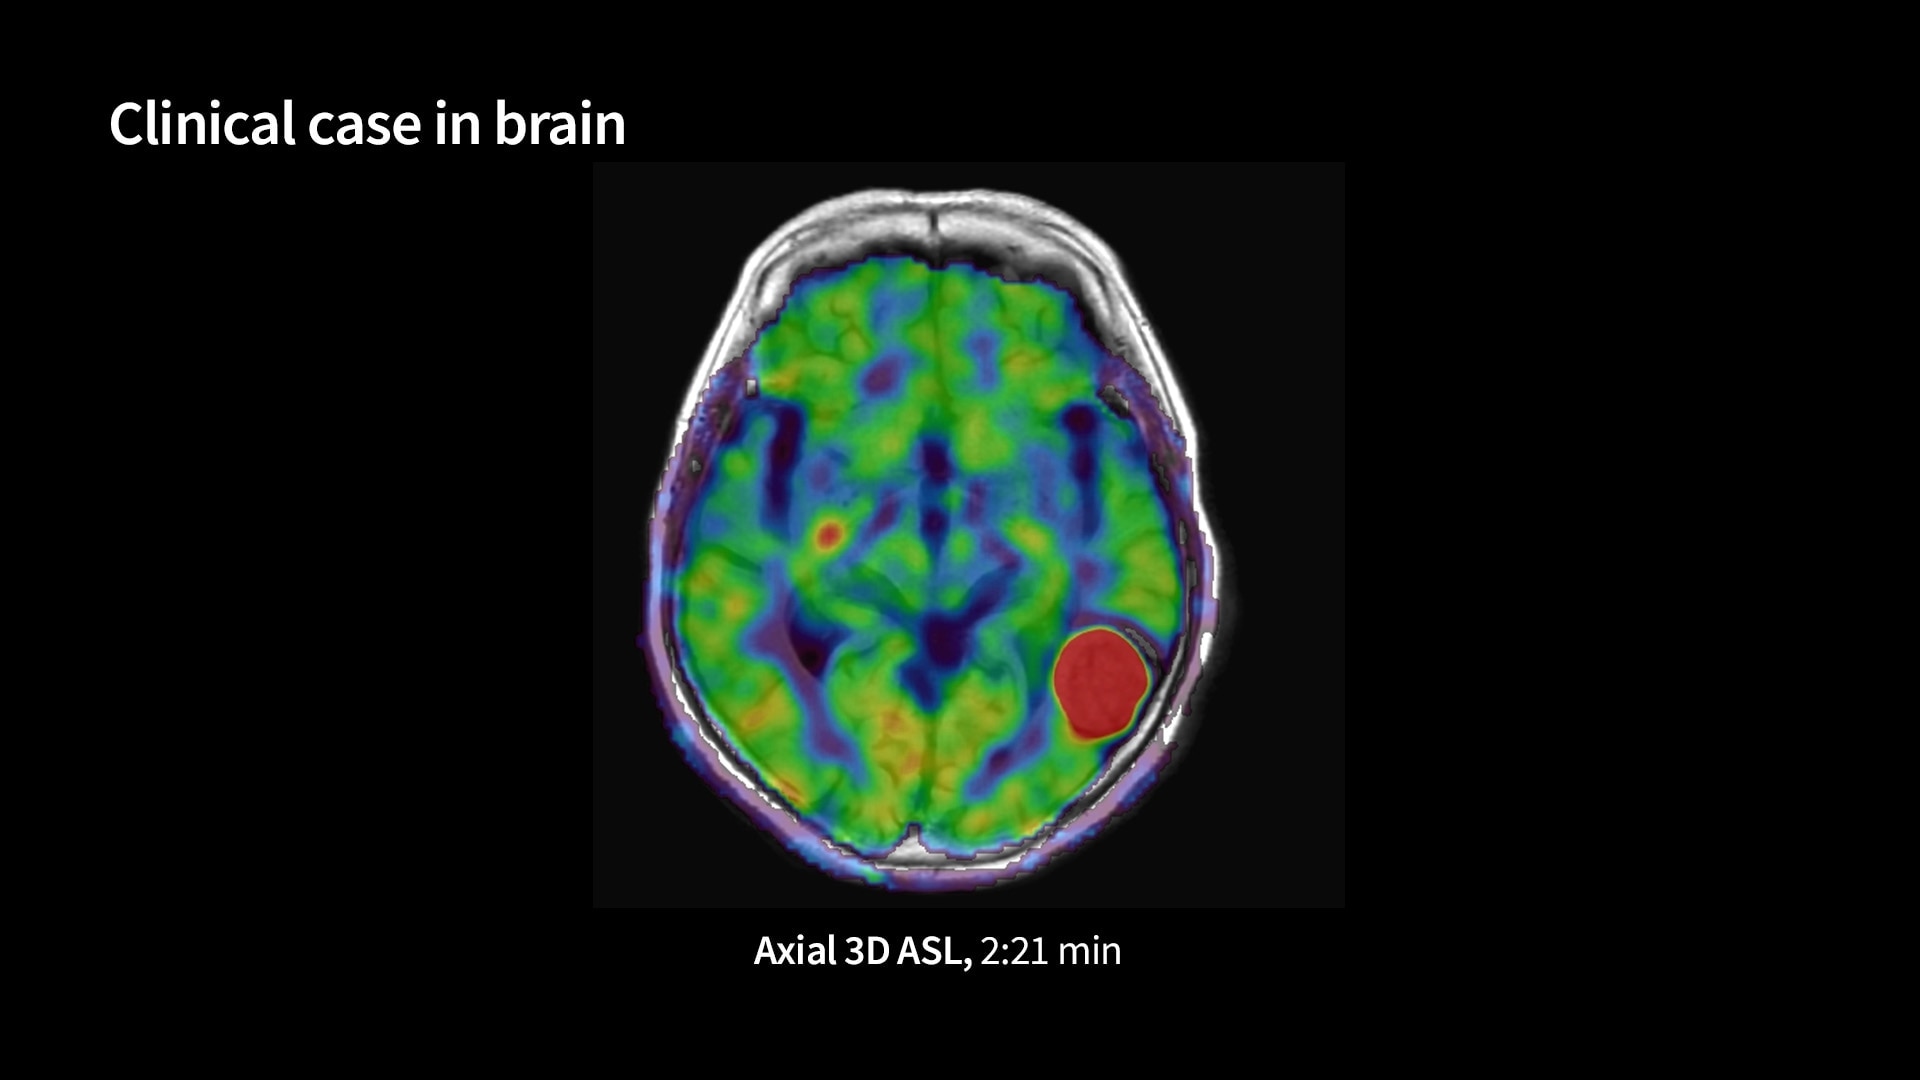

<p>3D Arterial Spin Labeling (3D ASL)</p>

Read case study ico-caret-right